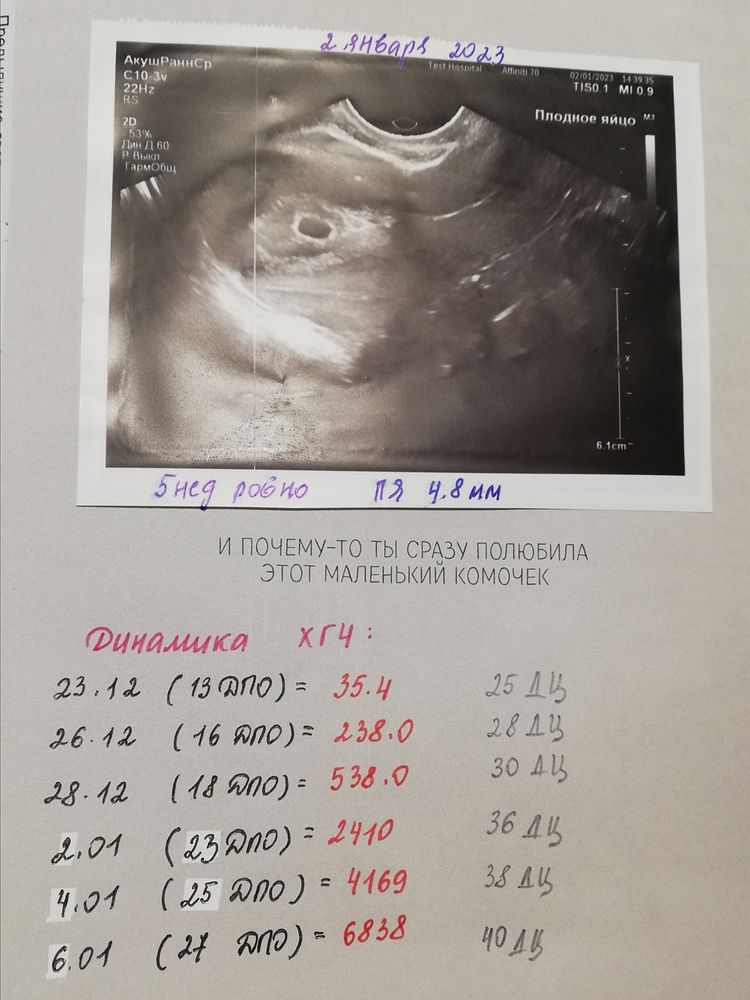

Natalya Natalie, вот это отчет в вас😀спасибо

Яна, пожалуйста 😁 я дотошная 😂 сохраняла на память) ну и отслеживала четко, тк лежала на сохранении с кровотечением 3 недели.